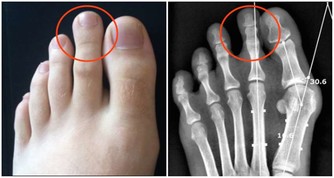

★避免人工關節手術,鬆緩肌肉消除膝蓋痛

58歲魏女士,數年來以玻尿酸治療膝蓋傷,最後惡化到須換人工關節。

經調整並配合強化操後,不能彎的膝蓋終於可以蹲下。